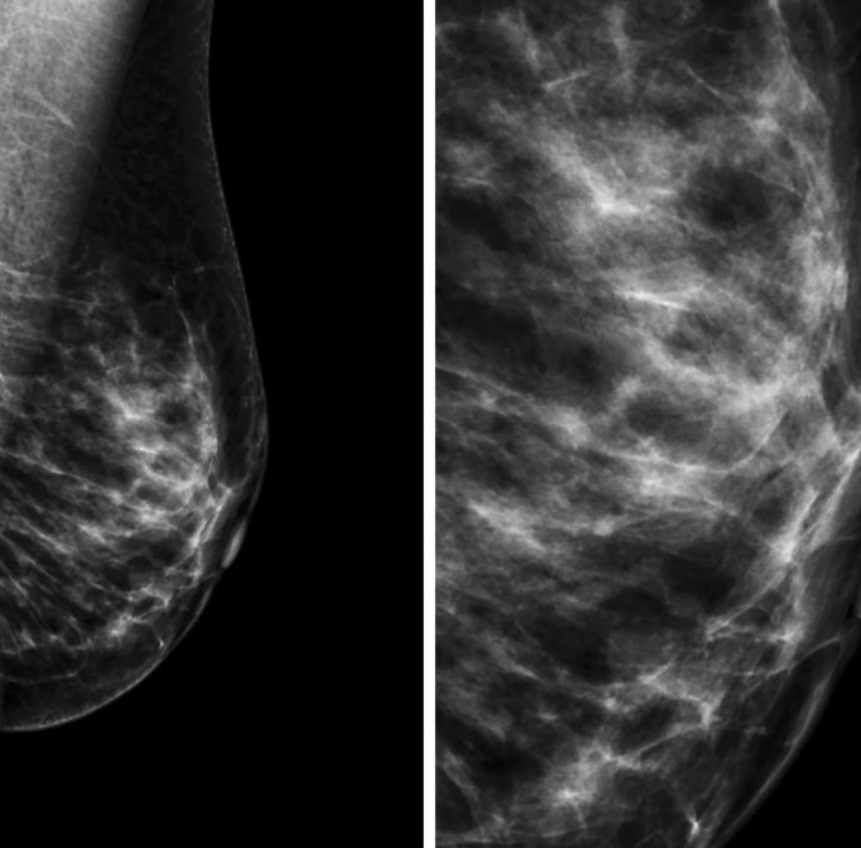

Сосудистые кальцинаты определяются на маммограммах как параллельные гиперденсные линии по ходу стенок сосудов. Их также называют кальцинатами Мёнкеберга, они поражают среднюю оболочку сосуда [13, 14] (Рис.2).